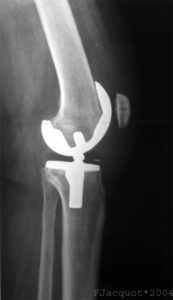

By evening the Sondernkommando [German: special operator] came creeping back by to try again to coax me up out of bed for a test flight of the new titanium joint and to see if my papers were in order; I was ever so thankful that they were. After strings of oaths and gnashing of teeth, I was vertical on a walker making a slow-motion loop around the nurses’ station.

We two bro’d around for a few minutes talking about women, whiskey, cigars, guns and MMA until he insisted he had to get for his first round knee replacement procedure of the day. I liked this guy immensely: he was a devout professional, serious, competent, personable and respectful.